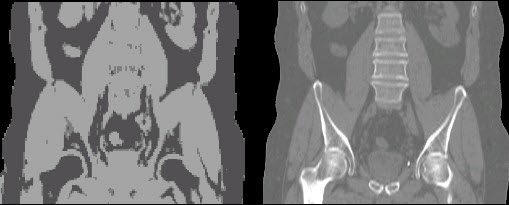

Multimodal imaging has become a critical resource across the medical field, as it effectively allows for diagnosing and monitoring the development and progression of a disease at both a molecular and anatomical level. While combined positron emission tomography and computerized tomography (PET/CT) is the most widely implemented form of multimodal imaging used today, a novel and innovative medical technology, known as a hybrid PET and magnetic resonance imaging (PET/MRI), has recently emerged. The quantitative PET data combined with the simultaneously acquired MRI information has the potential to provide clinicians with tumor metabolic information (PET), coupled with clear anatomical detail (MRI) of the desired soft tissue compartments. PET/MRI has gained widespread traction in recent years largely due to the fact that MRI eliminates exposure to ionizing radiation and offers excellent soft-tissue contrast. For certain applications such as prostate cancer (PCa), PET/MRI has the potential to become the leading imaging modality as it could allow clinicians to more confidently discriminate clinically relevant from non-life-threatening PCa lesions. However, before it can be used to guide patient management, a remaining methodological challenge needs to be addressed. Specifically, a method to perform PET attenuation correction based on the MR data needs to be developed and evaluated. Attenuation correction is especially important when imaging the pelvis, as bone tissue and air pockets surrounding the prostate are often misclassified as soft tissue (see image), leading to PET quantification bias and artifacts. In this project, we will compare the performance of several deep learning approaches to generate pelvis attenuation maps from the MR images using data acquired from PCa patients. After attenuation is properly accounted for, both radiomics and deep learning approaches can be employed to identify the most relevant imaging features from each modality and combine them into a multimodal classification model that best characterizes primary prostate tumor aggressiveness.